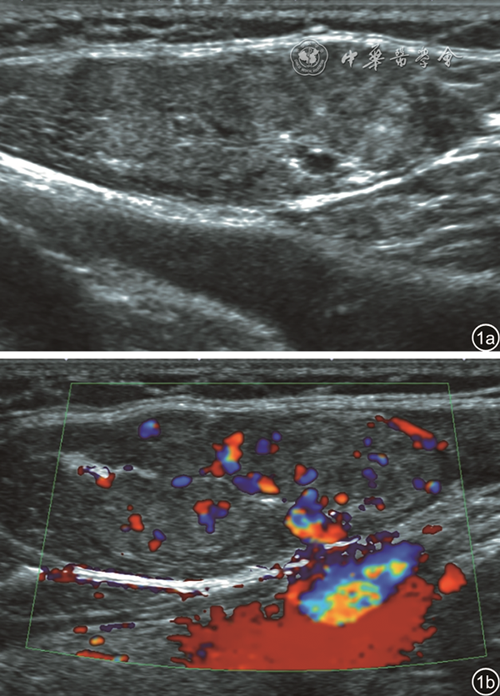

颈纤维瘤病为胸锁乳突肌损伤后的纤维组织增生性浸润改变,可能与产伤引起的肌肉内静脉栓塞有关28,超声可做出明确诊断。患儿出生后2~3周即可出现症状,主要表现可能为斜颈或颈部包块。在超声上表现为胸锁乳突肌呈梭形增大或局部肿块,可表现为高回声、高低混杂回声,肌纹理不清,彩色多普勒超声通常显示血流信号增多(图129

图1 颈纤维瘤病超声表现。图a:胸锁乳突肌局部呈高低混杂回声,肌纹理不清;图b:彩色多普勒成像示血流信号增多